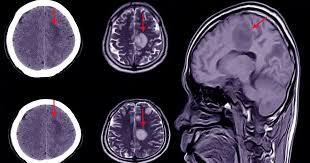

Es una lesión cerebral que también puede afectar gravemente al cuerpo. Se produce cuando se interrumpe el riego sanguíneo a una parte del cerebro o cuando se produce un derrame de sangre en el cerebro o alrededor de él.

ACV isquémico

Se produce cuando el flujo sanguíneo al cerebro se interrumpe debido a un bloqueo en una arteria, comúnmente ocasionado por un coágulo de sangre o la acumulación de placas de ateroma (aterosclerosis).

Este tipo de accidente cerebrovascular representa aproximadamente el 80% de todos los casos de ACV y puede llevar a la muerte de células cerebrales si no se restablece el flujo sanguíneo rápidamente

Ocurre cuando un vaso sanguíneo en el cerebro se rompe, provocando sangrado en el tejido cerebral o en el espacio que lo rodea. Esto no solo interrumpe el suministro de sangre a las áreas afectadas, sino que también puede causar presión en otras partes del cerebro, con un potencial daño adicional.

Este tipo representa alrededor del 20% de los accidentes cerebrovasculares.

SECUELAS COGNITIVAS

Las secuelas cognitivas son alteraciones en las habilidades mentales que pueden surgir tras un ACV